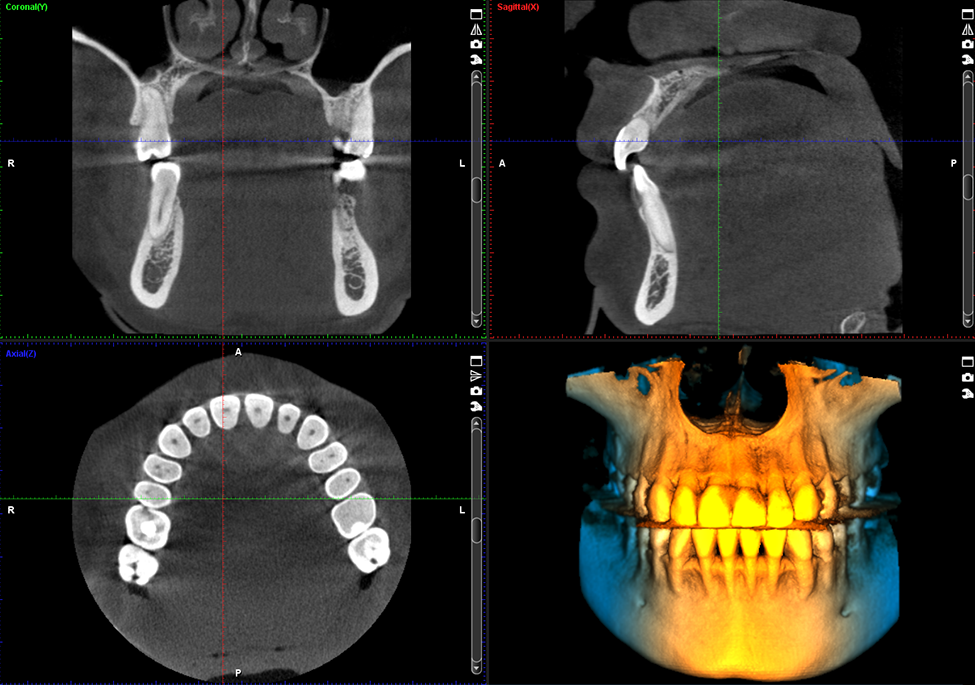

Dental Imaging

img01

Planmeca ProMax 3D

• Low-radiation 3D CBCT scans for safer, more accurate diagnosis of teeth, jaw, and sinus problems.

• Fast and comfortable imaging completed in seconds.

• 3D facial photo with zero radiation to help plan cosmetic and orthodontic treatments more precisely.

• Precise digital models for better-fitting treatments like implants, aligners, and restorations.